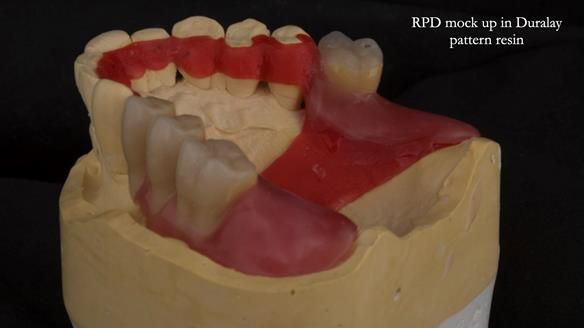

Instead, we made a Scandinavian-style, metal-based lower RPD.

It’s worth saying that the lower denture in this case was made in the early days of Rowan and me using the Scandinavian approach. Rowan cast the metalwork himself for this denture.

Looking back, we would make this denture more hygienic now. The design and finish would be more refined and delicate, particularly when compared with the upper metalwork, which was made later using Chris Hesketh’s chrome work. I will discuss this in detail at the study club.

That said, the lower denture worked beautifully. It did exactly what it was meant to do, even though, by today’s standards, it looks a little agricultural.